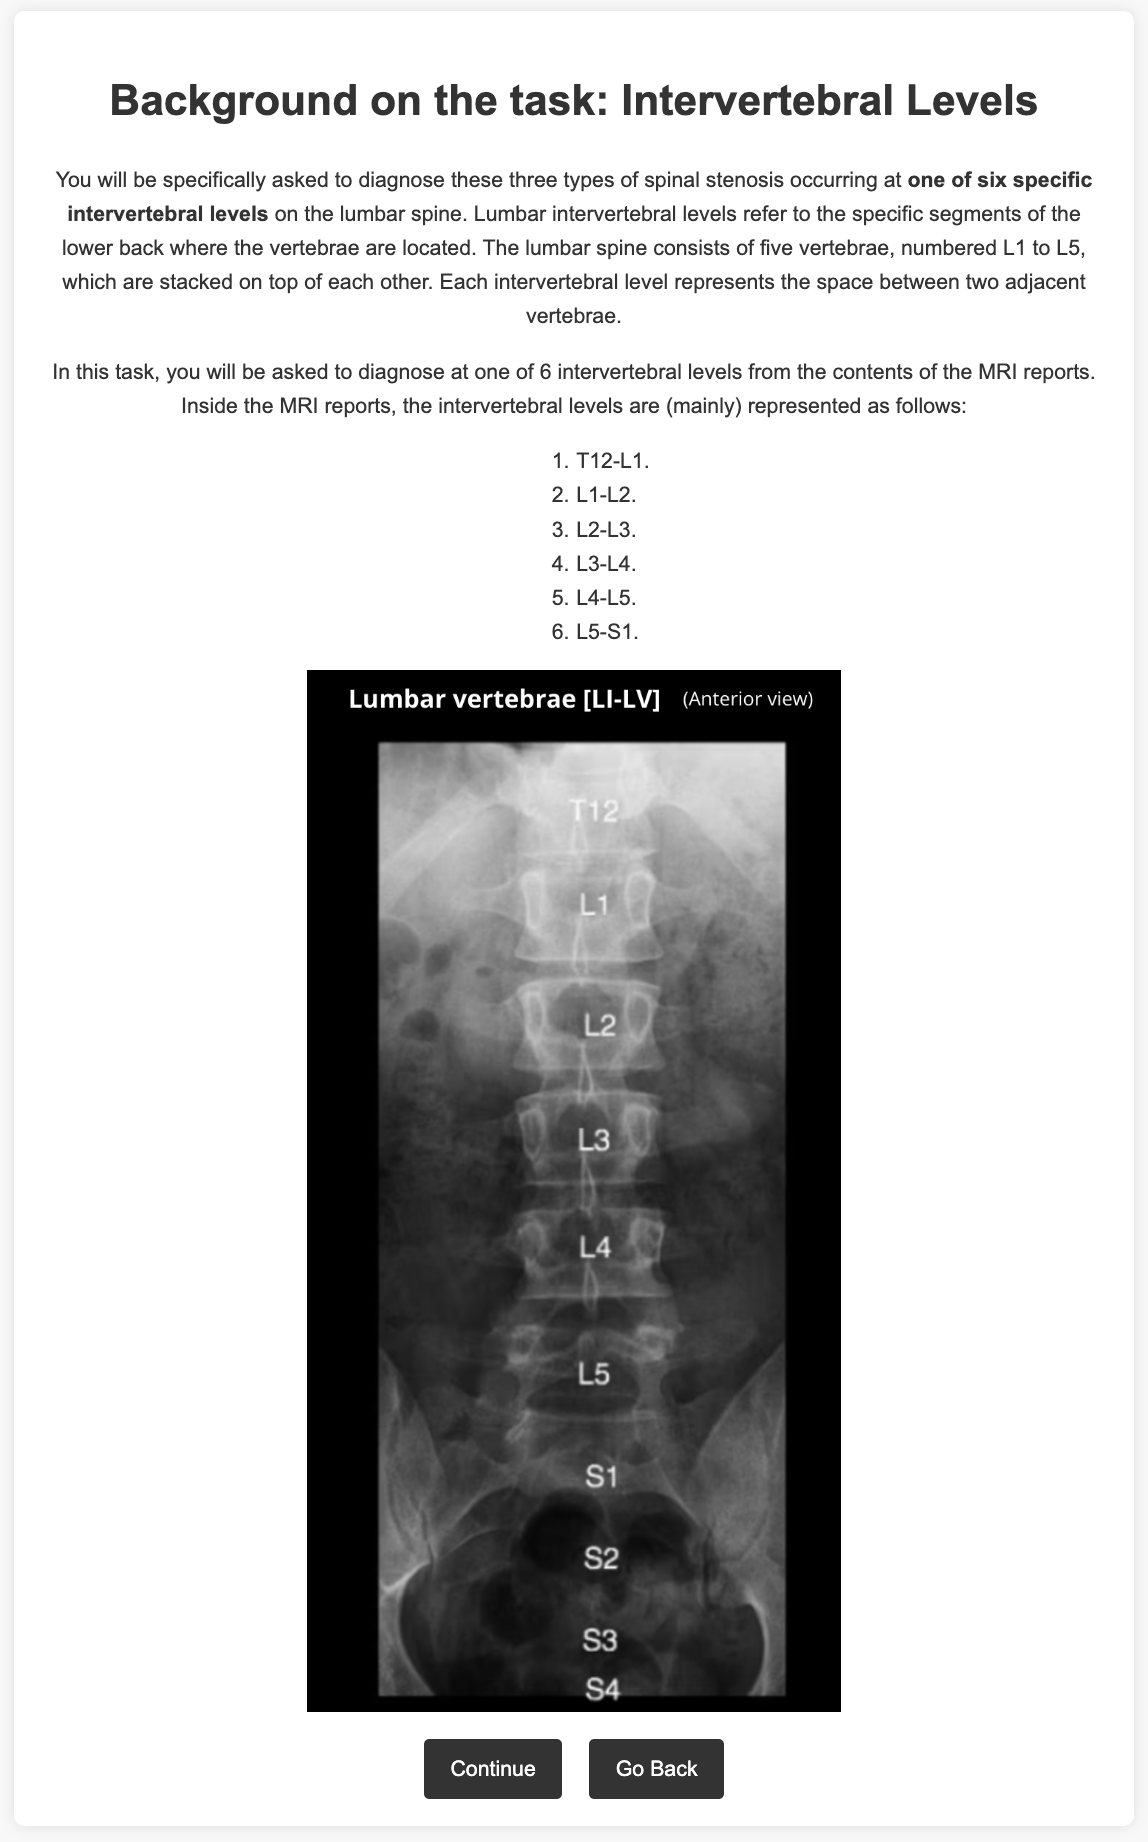

We use the OSCLMRIC (Oxford Secondary Care Lumbar MRI Cohort) dataset, containing professionally annotated lumbar MRIs and radiological reports for various types of stenosis at different spinal levels, of which serve as our ground-truth labels. An example report is shown in Listing LABEL:lst:example_report. The dataset is highly imbalanced, with 95% of labels negative. Each report is parsed to detect the binary presence of three types of spinal stenosis (foraminal stenosis [FS], spinal canal stenosis [SCS], and lateral recess stenosis [LRS]) at six lumbar spine levels, resulting in 1,800 examples. The data is randomly split into 30% for generating an instruction-tuning dataset, 20% for training the hidden-state classifier, 20% for validation, and 30% for testing.